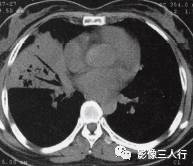

由于实变的肺组织与含气的支气管相衬托,在实变区中可见透明的支气管影即空气 支气管征,临床常见于大叶性肺炎的实变期,包括红色肝样变及灰色肝样变期,表现为密度均匀的致密影内可见透明的支气管影(图1)。这一征象被认为是肺泡炎性病变的有力证据。 医学百科网 | YxBaike.Com